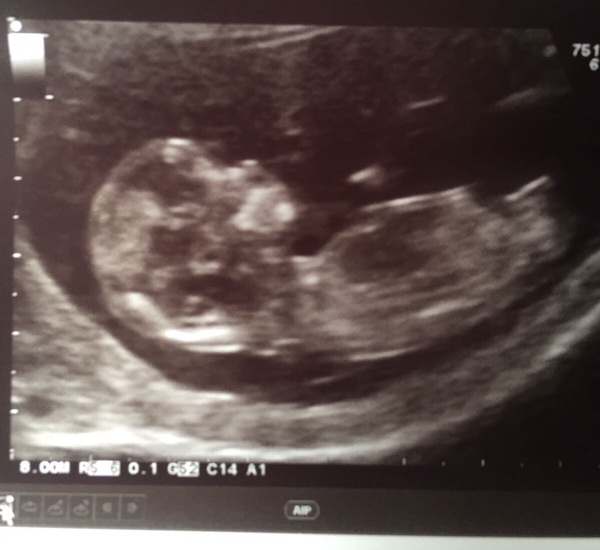

We had our 12 week scan this morning and everything is great. It's so amazing to see the baby moving about on the screen. At 9 weeks, it was just a blob, it's grown so much!! I measured 2 days ahead which is odd as I was sure I was later due to Ov date but I'm not arguing! Due date 30th Nov.

#TTC1 - Second Wave grads thread the Second!